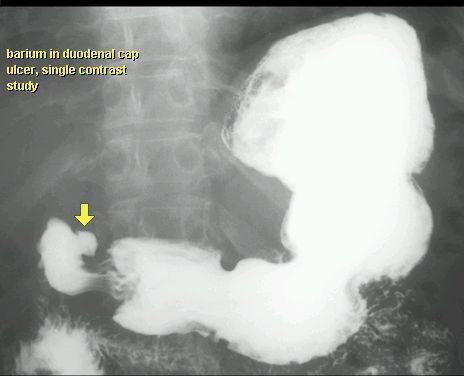

WRZÓD DWUNASTNICY

KONTRAST DO GOPP